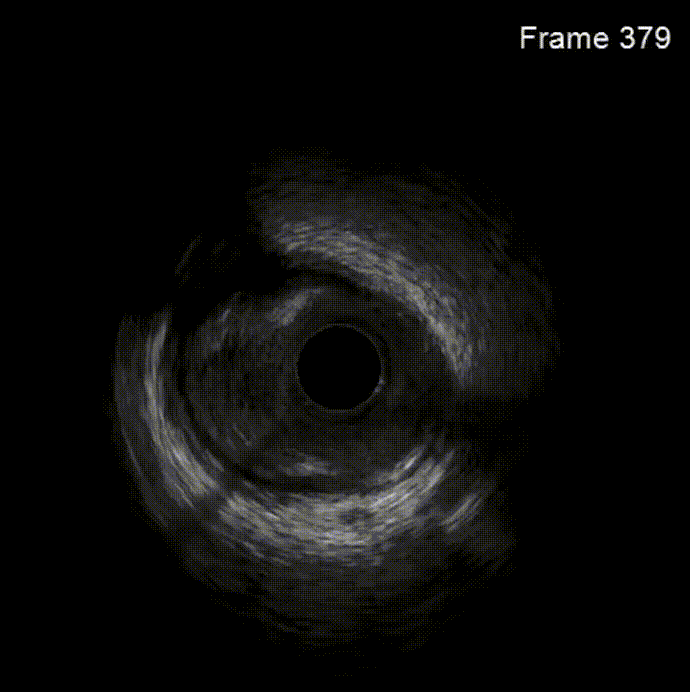

随后进一步行左冠PCI,因病变涉及主干并存在严重钙化,故使用IVUS进行指导。IVUS可见LM中段60%-70%斑块负荷,呈纤维性斑块伴浅表点状钙化,最小管腔面积(MLA)5.79mm²;LAD近中段弥漫性180°-270˚钙化狭窄,局部钙化小洁突入管腔,最小管腔面积2.99mm²;LCX开口50%斑块负荷,开口管腔截面积5.01mm²。

根据IVUS结果,可选用CROSSOVER术式,前降支病变有IVL预处理指征。基于IVUS的测量参数选择赛禾3.0*12mm冲击波球囊在4atm压力下释放冲击波脉冲3个周期。可见球囊逐渐膨胀充分,复查IVUS可见LAD近中段钙化环完全裂解,预处理效果满意。